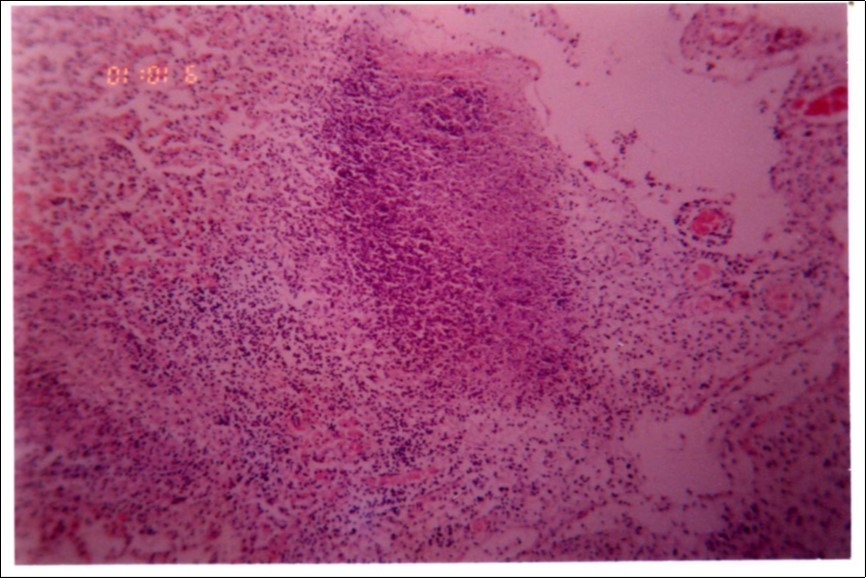

Figure 3, Figure 4 and Figure 5 show different histopathological pictures of hepatized lung tissue samples from which Mmm isolates were recovered. In Figure 3, widened interlobular septa, due to presence of fibrinous necrosis and cellular infiltration were observed. Figure 4 shows extensive loss of airspace due to necrosis and infiltration of neutrophils. Figure 5 shows hyperemia of alveolar wall capillaries and infiltration of few fibrin and neutrophils.

Figure 4.Extensive loss of air space due to necrosis and infiltration of neutrophils (H&E ×100).

Extensive loss of air space due to necrosis and infiltration of neutrophils (H&E ×100).

Although no advanced techniques like PCR were used to identify the isolates, procedures used in this study were quite enough to confirm the incidence. Affected animals with CBPP were diagnosed based on the clinical signs, the PM findings, the typical histopathological picture in addition to the isolation of the causative agent and its subsequent identification using cultural and biochemical procedures. Identification of the isolates was confirmed by the growth inhibition test as recommended in OIE manual 10. The histopathological sections of diseased lungs, from which Mmm (SC) was isolated, showed typical histopathological picture of CBPP. The CBPP lesion comprises abronchiolar necrosis and oedema which progress rapidly to an exudative serofibrinous bronchiolitis with extension to the alveoli and uptake of alveolar fluid into tissue spaces 17, lymphatic vessels and ultimately septal lymphatics 18. With stasis, lymphatic vessels become thrombosed and ultimately fibrosed 19. The histological section of the lung in acute stage of the disease showed odema in the lymphatics of the interlobular septa and interstitial tissue and massive infiltration of fibrin, macrophage and neutrophils into the alveolar lumen 20. Also there was presence of lymphocytes and alveolar macrophages around the lymphatic vessels and septa margin 21. These findings supported the isolation results and gave additional evidence for the diagnosis of the disease.